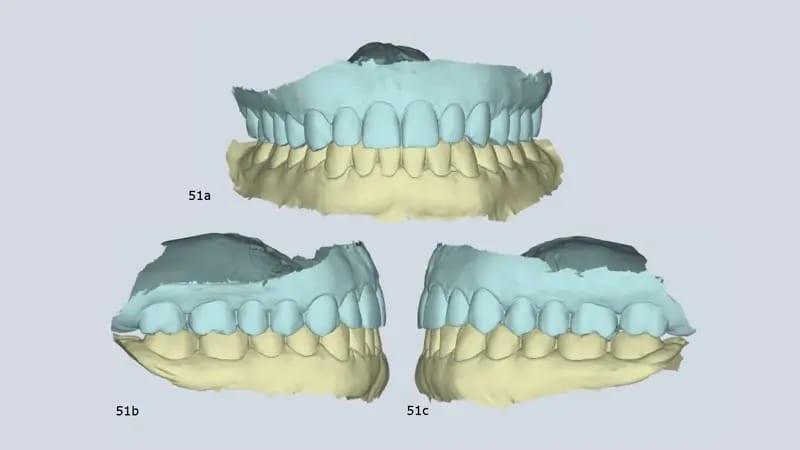

Наконец, в результате лечения была достигнута ортопедическая стабильность (максимальная интеркуспация совпала с центральной окклюзией), а также улучшилось положение и морфология мыщелков. У пациентки также полностью отсутствовали симптомы ВНЧС (фото 51).

Фото 51a–c: Крепление виртуального артикулятора с помощью MODJAW, демонстрирующее ортопедическую стабильность.